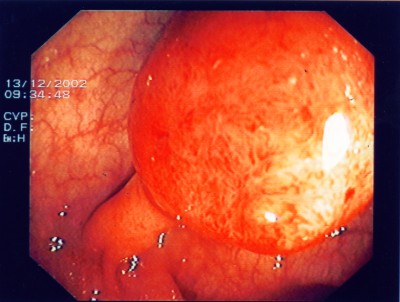

Großer Polyp des Dickdarmes